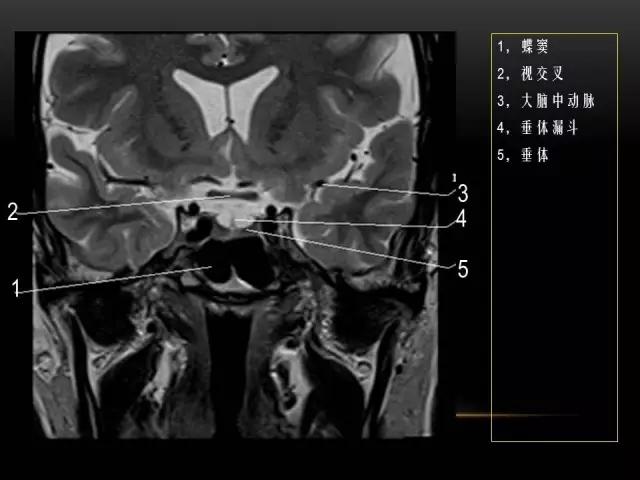

下文是在MRI下眼部及鼻窦的冠状位解剖图谱。